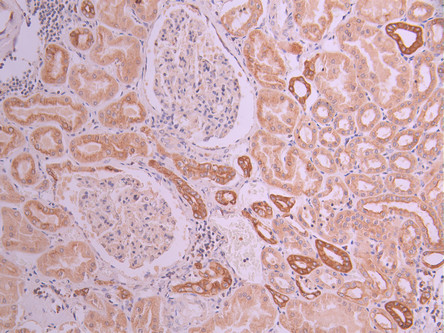

• IHC image of CSB-RA050869A0HU diluted at 1:100 and staining in paraffin-embedded human kidney tissue performed on a Leica BondTM system. After dewaxing and hydration, antigen retrieval was mediated by high pressure in a citrate buffer (pH 6.0). Section was blocked with 10% normal goat serum 30min at RT. Then primary antibody (1% BSA) was incubated at 4°C overnight. The primary is detected by a Goat anti-rabbit polymer IgG labeled by HRP and visualized using 0.05% DAB.